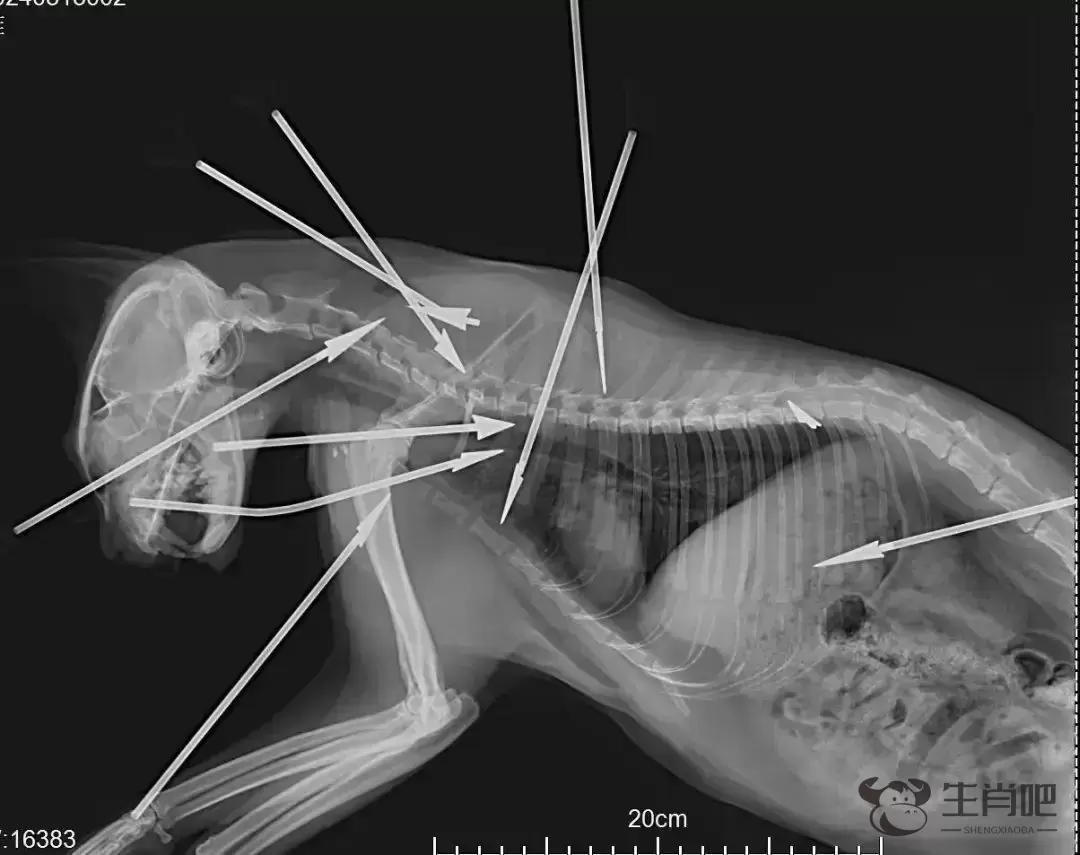

猫咪救助志愿者张女士提供的照片显示,狸白猫的头部、胸部和背部总共被射入9支箭,而根据X光片,还有一个断了的箭头留在猫咪体内,也就是说,狸白猫总共中了10箭。因伤势过重,最终这只猫咪抢救无效死亡。

8月14日,收治了狸白猫的医院工作人员告诉记者,狸白猫被送到医院时状态已经很差,这只猫身中10箭(包括体内箭头),尤为严重的是,其中一支箭从猫的鼻部贯穿至咽喉,一支箭刺穿了它的肺部。抢救约1个半小时后,猫咪被确认死亡。